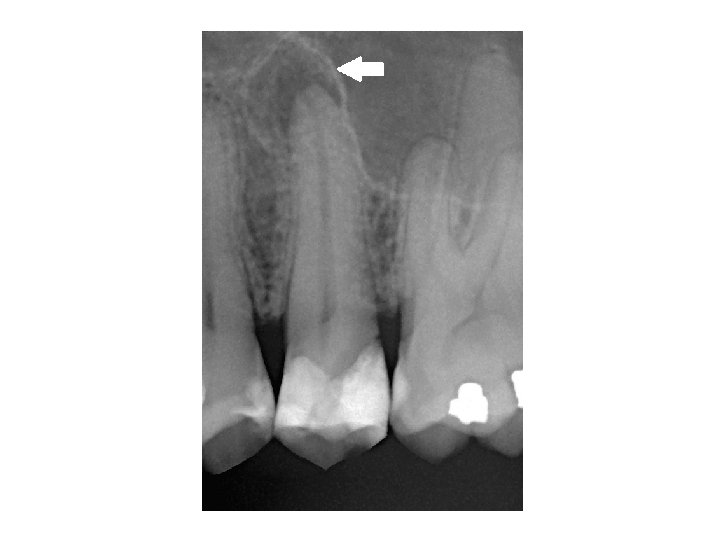

Parodontitis lateralis chronica • Es gibt Seitekanale nach mesiale oder nach distale Richtung. Die Veränderung erscheint neben der Wurzel. • Symptome: Keine Schmerzen, Devitalität des betroffenen Zahnes. • Röntgen: rundliche Aufhellung im lateralen Parodontium.